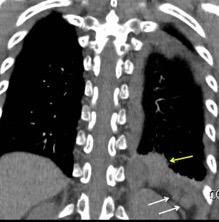

Signos radiológicos TC

Hallifax RJ et al. State-of-the-art: Radiological investigation of pleural disease Respiratory Medicine 2017

Nivel hidroaéreo o burbujas

Forma lenticular o elíptica Ángulos obtusos

> Grasa Extrapleural (60-80%)

Situación no gravitacional (no siempre)

Compresión de estructuras pulmonares

Límite muy bien definido Tabicación

Signo de la Pleura separada “Split pleural sign”

Capas pleurales de grosor uniforme realzadas por el contraste

No específico de empiema. Indica “exudado”. 68% de pacientes con empiema pleural.

Capas pleurales de grosor uniforme

Realce grasa extrapleural (30%)

> Grasa Extrapleural. (60-80%)

Kraus GJ. Split pleural sign. Radiology 2007